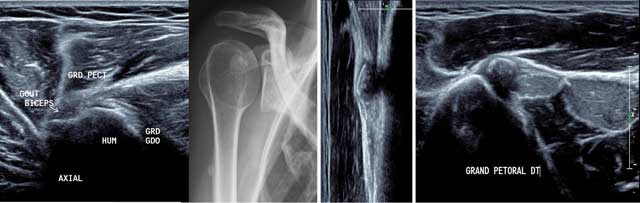

Injuries are mainly traumatic onto the tendon insertion or myotendinous junction. But in the context of previous shoulder pain, enthesopathies are also described [11]. At ultrasound exploration is performed in sagittal plane from the humeral insertion to the sternum searching for an architectural disorganization, hematoma or asymmetry compared to the opposite side plus by contraction and the ABER position (abduction external rotation) (Figure 16).

Figure 16

Axial view of the normal anterior part of the humerus in external position (a) with hydroxyapatite deposits in X-rays (b) and US in sagittal and axial view (d). GRD/GDO: Teres Major/Latissimus Dorsi, GRD PECT: Pectoralis Major, HUM: Humerus, Court Biceps: Short head of the biceps.